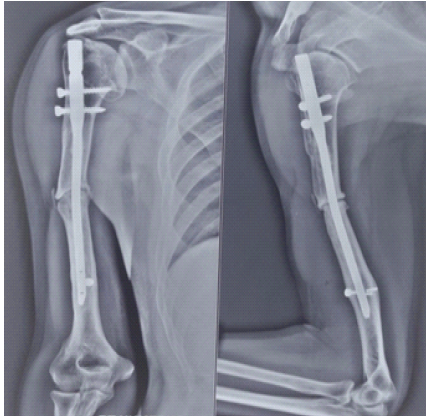

In April 2024, the patient developed vague, chronic pain at the fracture site and was evaluated by a nearby orthopedic surgeon. Anteroposterior and lateral radiographs of the right humerus demonstrated a mid-diaphyseal non-union with a persistent fracture line, sclerotic fracture margins, and an IMIL nail in situ. Surgical intervention was advised; however, the patient did not comply with follow-up as recommended (Fig. 2).

Figure 2: Anteroposterior and lateral radiographs of the right humerus taken in April 2024 demonstrating mid-diaphyseal non-union with a persistent fracture line, sclerotic bone ends, and an intramedullary interlocking nail in situ.